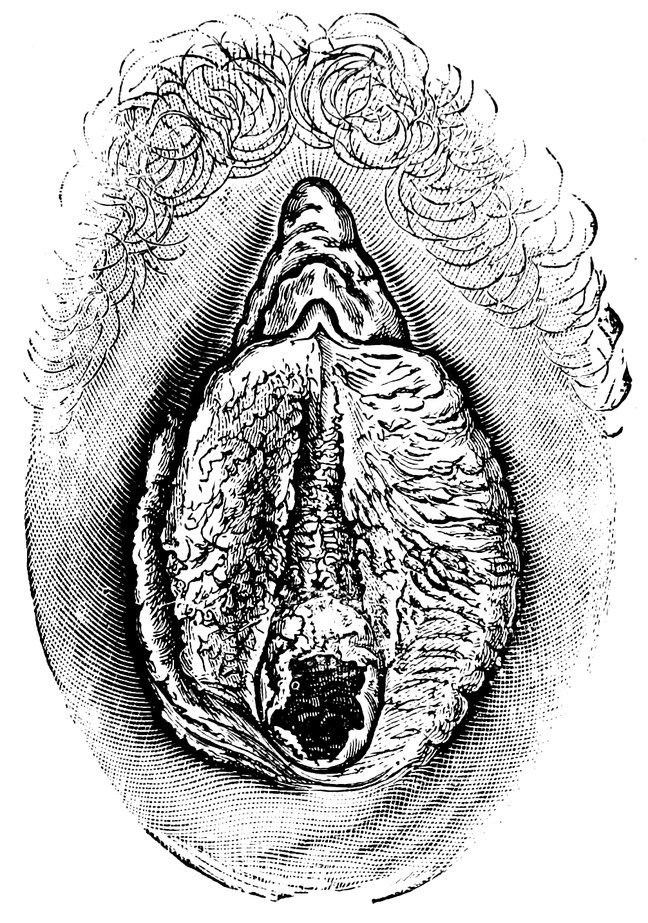

| 12. | Female external genital organs of a virgin | 54 |

| 13. | The external genital organs of a virgin | 55 |

| 48. | The female pudendum, or vulva, with the labia majora | 204 |

| 51. | Female internal genital organs in the fully developed state | 208 |